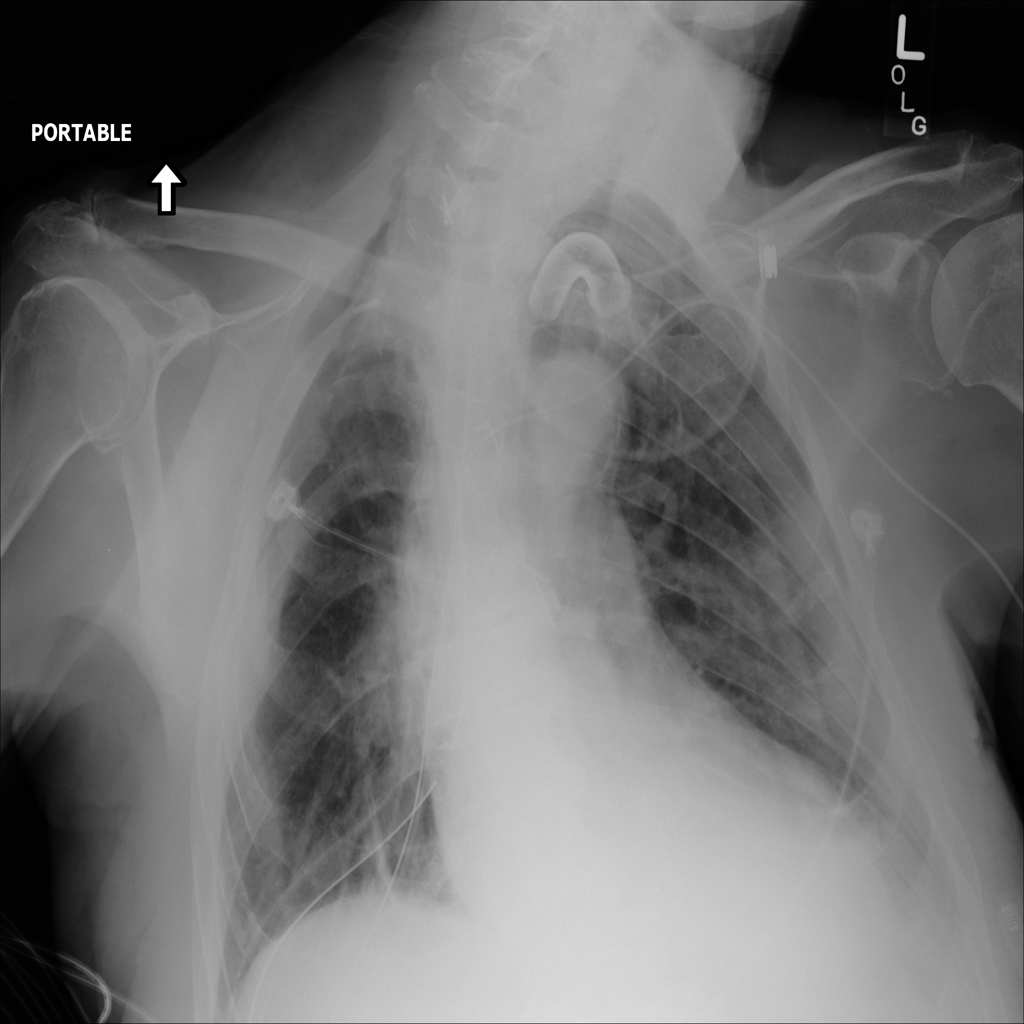

PAT-595E · IMG-010Atelectasis

PAT-595E · IMG-010

AP

PAT-8B05 · IMG-001Atelectasis

PAT-8B05 · IMG-001